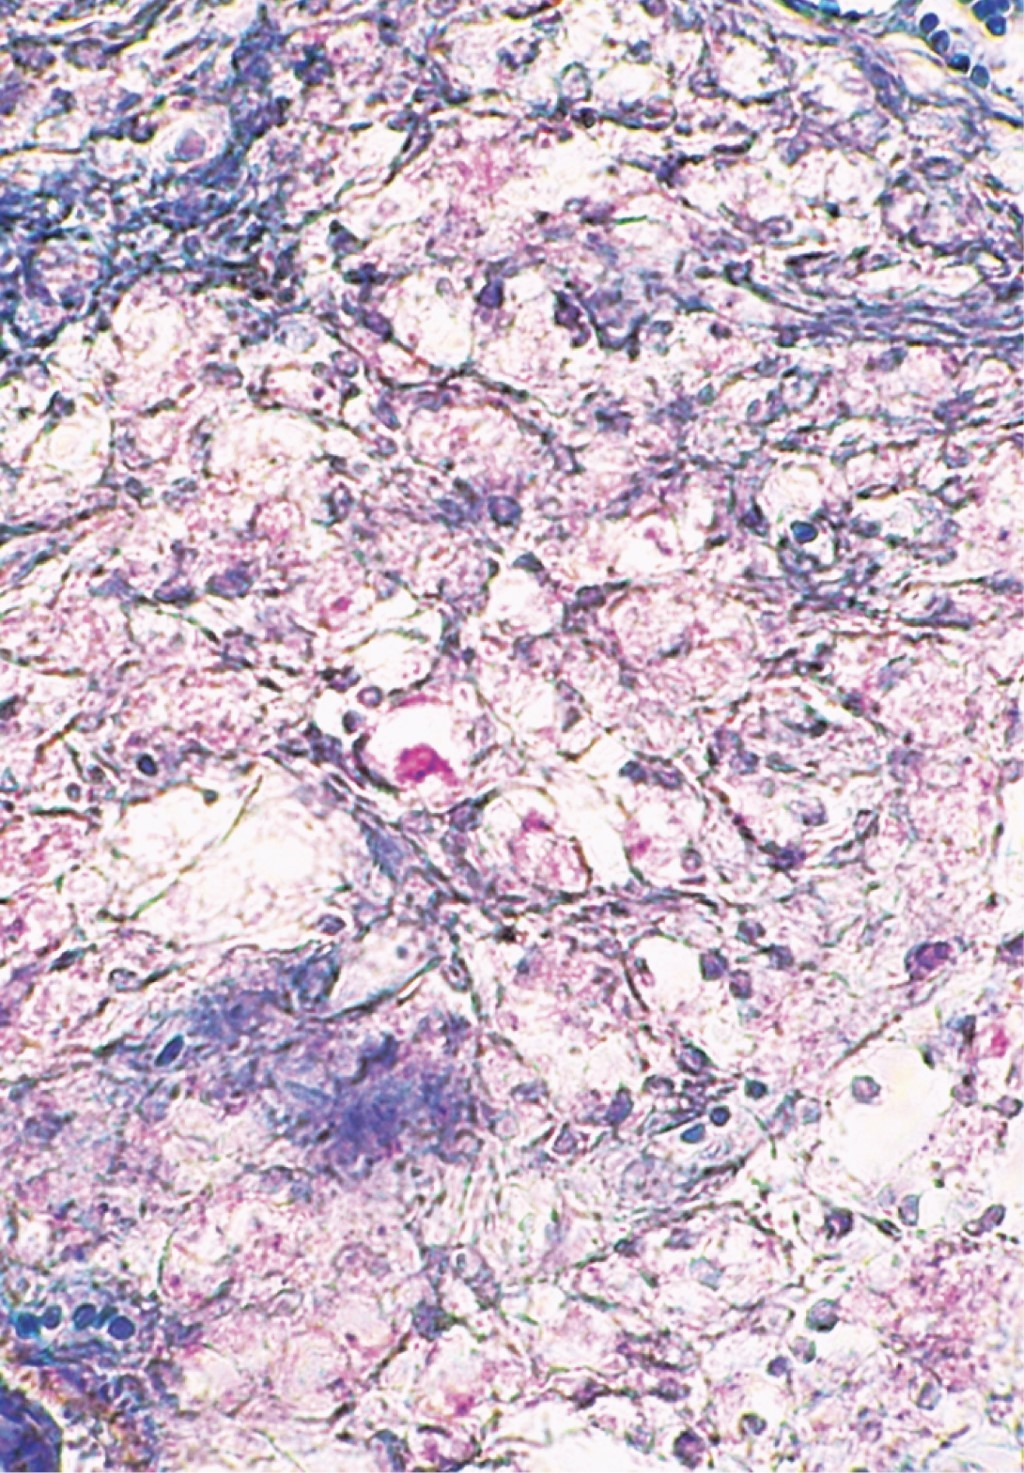

Se realiza biopsia incisional y el estudio histopatológico con tinción de rutina muestra: epidermis atrófica con hiperqueratosis ortoqueratósica, formación de tapones córneos e hiperpigmentación de la capa basal. En algunas zonas de la dermis superficial se observa la presencia de edema entre las fibras colágenas así como infiltrados moderados focales que tienden a rodear algunos vasos dilatados y congestionados. Estos infiltrados aumentan en intensidad y se observan ocupando la dermis media y profunda, e incluso hasta tejido celular subcutáneo. Están constituidos por abundantes histiocitos vacuolados, mismos que son más evidentes en las partes profundas del corte; además se aprecian linfocitos, histiocitos y numerosos polimorfonucleares que se ubican de manera predominante en las partes profundas de la epidermis y tejido celular subcutáneo, disponiéndose al nivel de los lóbulos grasos. Se aprecia edema en algunos sitios de la dermis profunda. Los infiltrados también tienden a rodear en algunos sitios a fibras nerviosas engrosadas. La tinción para bacilos fue positiva (Figuras 4, 5 y 6).

Figura 5

Figura 6